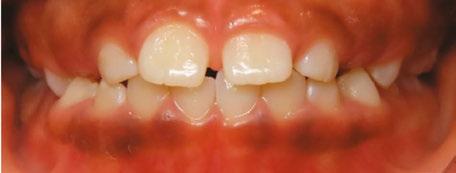

An 8-year-old Hispanic male presented to our private practice in Miami, Florida with the chief complaint of a missing front tooth (Figure 1). Upon review of his medical history, the mother revealed that her son had Autism Spectrum Disorder and confirmed that his condition was severe. This patient did not take

12 Orthodontic Practice US Volume 14 Number 2 CLINICAL

Figure 1: Face of 8-year-old patient at initial consultation